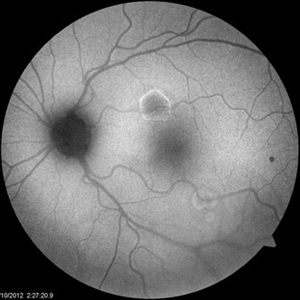

Aquired Vitelliform Maculopathy

Asymptomatic MA healthy female consulted for wet AMD. Plan: observe. Photo and AF initially and year afterwards. Health MA female; no vitritis or other lesions; similar findings in both eyes.

Photographer: Wayne A Ladlee Jr

Condition/keywords: aquired vitelliform maculopathy